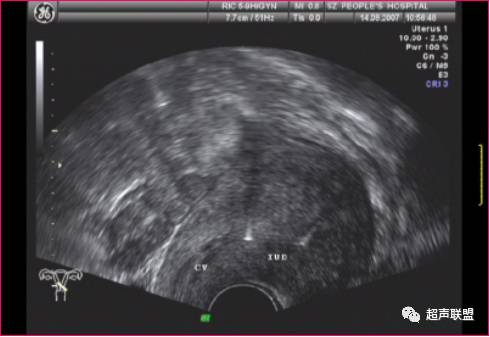

(经阴道超声)

节育环(IUD)位于宫颈(CX)左侧的盆腔内.

由于宫内节育器的形状、质地不同,其超声表现不尽相同。金属圆环和宫形环在二维超声扫查子宫纵切面表现为宫腔内两个分离的强回声,在其后方,由于产生多次反射形成慧尾征。T形环在子宫纵切面显示为宫腔内线状或串珠状强回声,横切面在宫腔底部显示条形强回声,塑料节育器在不同的切面扫查进表现为宫腔内强回声,其后方不伴慧尾征。

声像特点为节育器不在宫腔内而向下移位,节育器下缘达宫颈内口或内口以下,剖宫产切口处常形成憩室,也可是节育器下移到达之处,有时节育器可下移至宫颈管内,或脱出宫颈外口至阴道。

一般节育器的上缘距宫腔底内膜以下一段距离,或上缘距宫底大于2cm即诊断为宫内节育器下移。